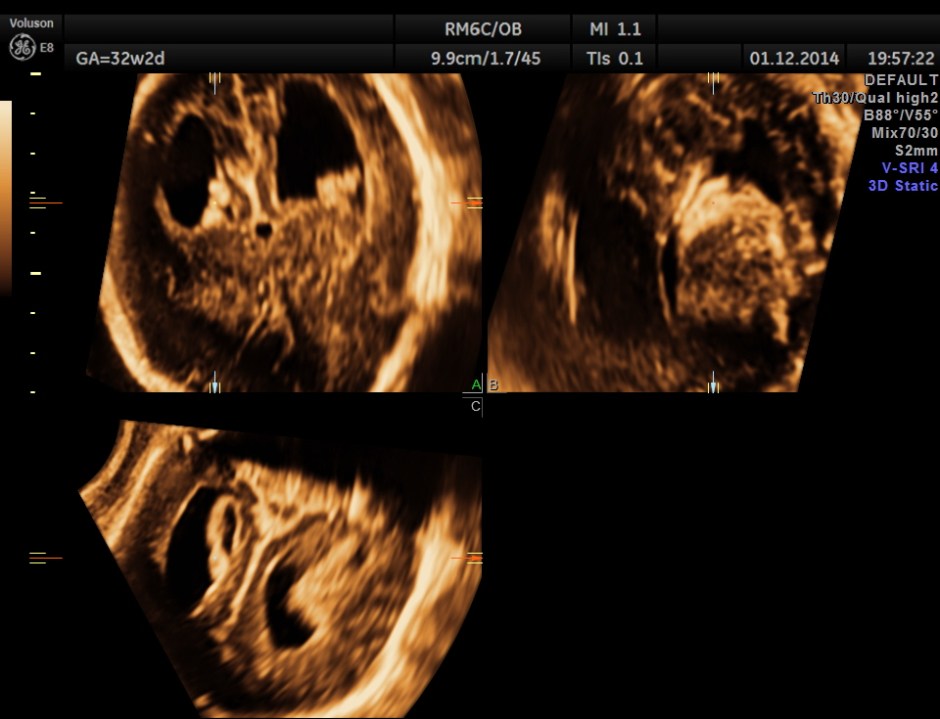

3D view of the same.